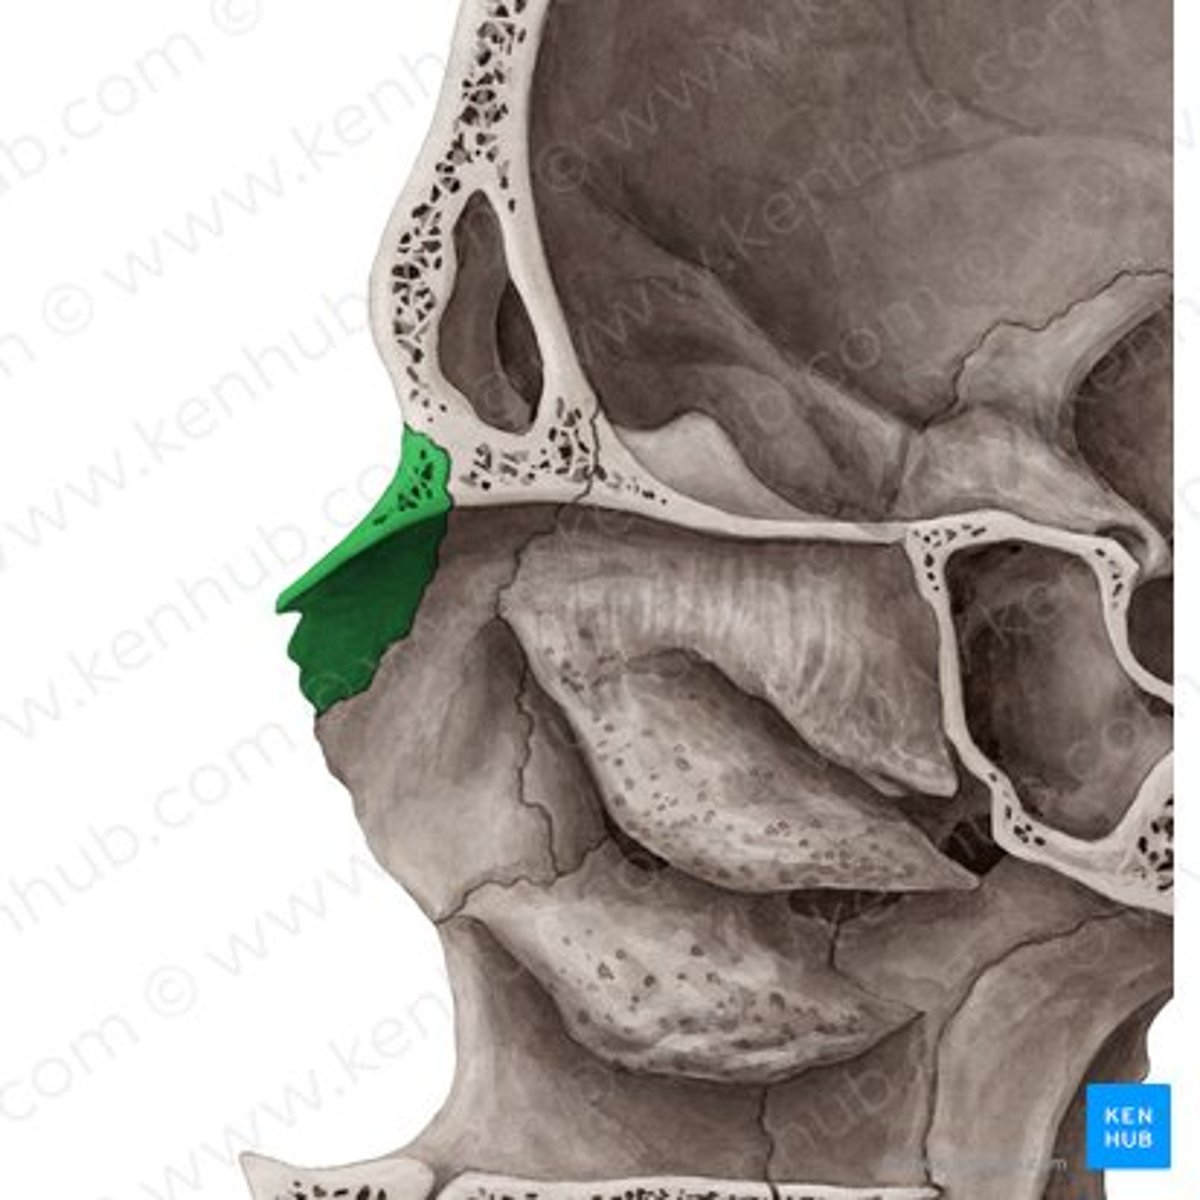

cribriform plate

anterior cranial fossa

frontal bone

nasal bone

ethmoid bone (perpendicular plate)